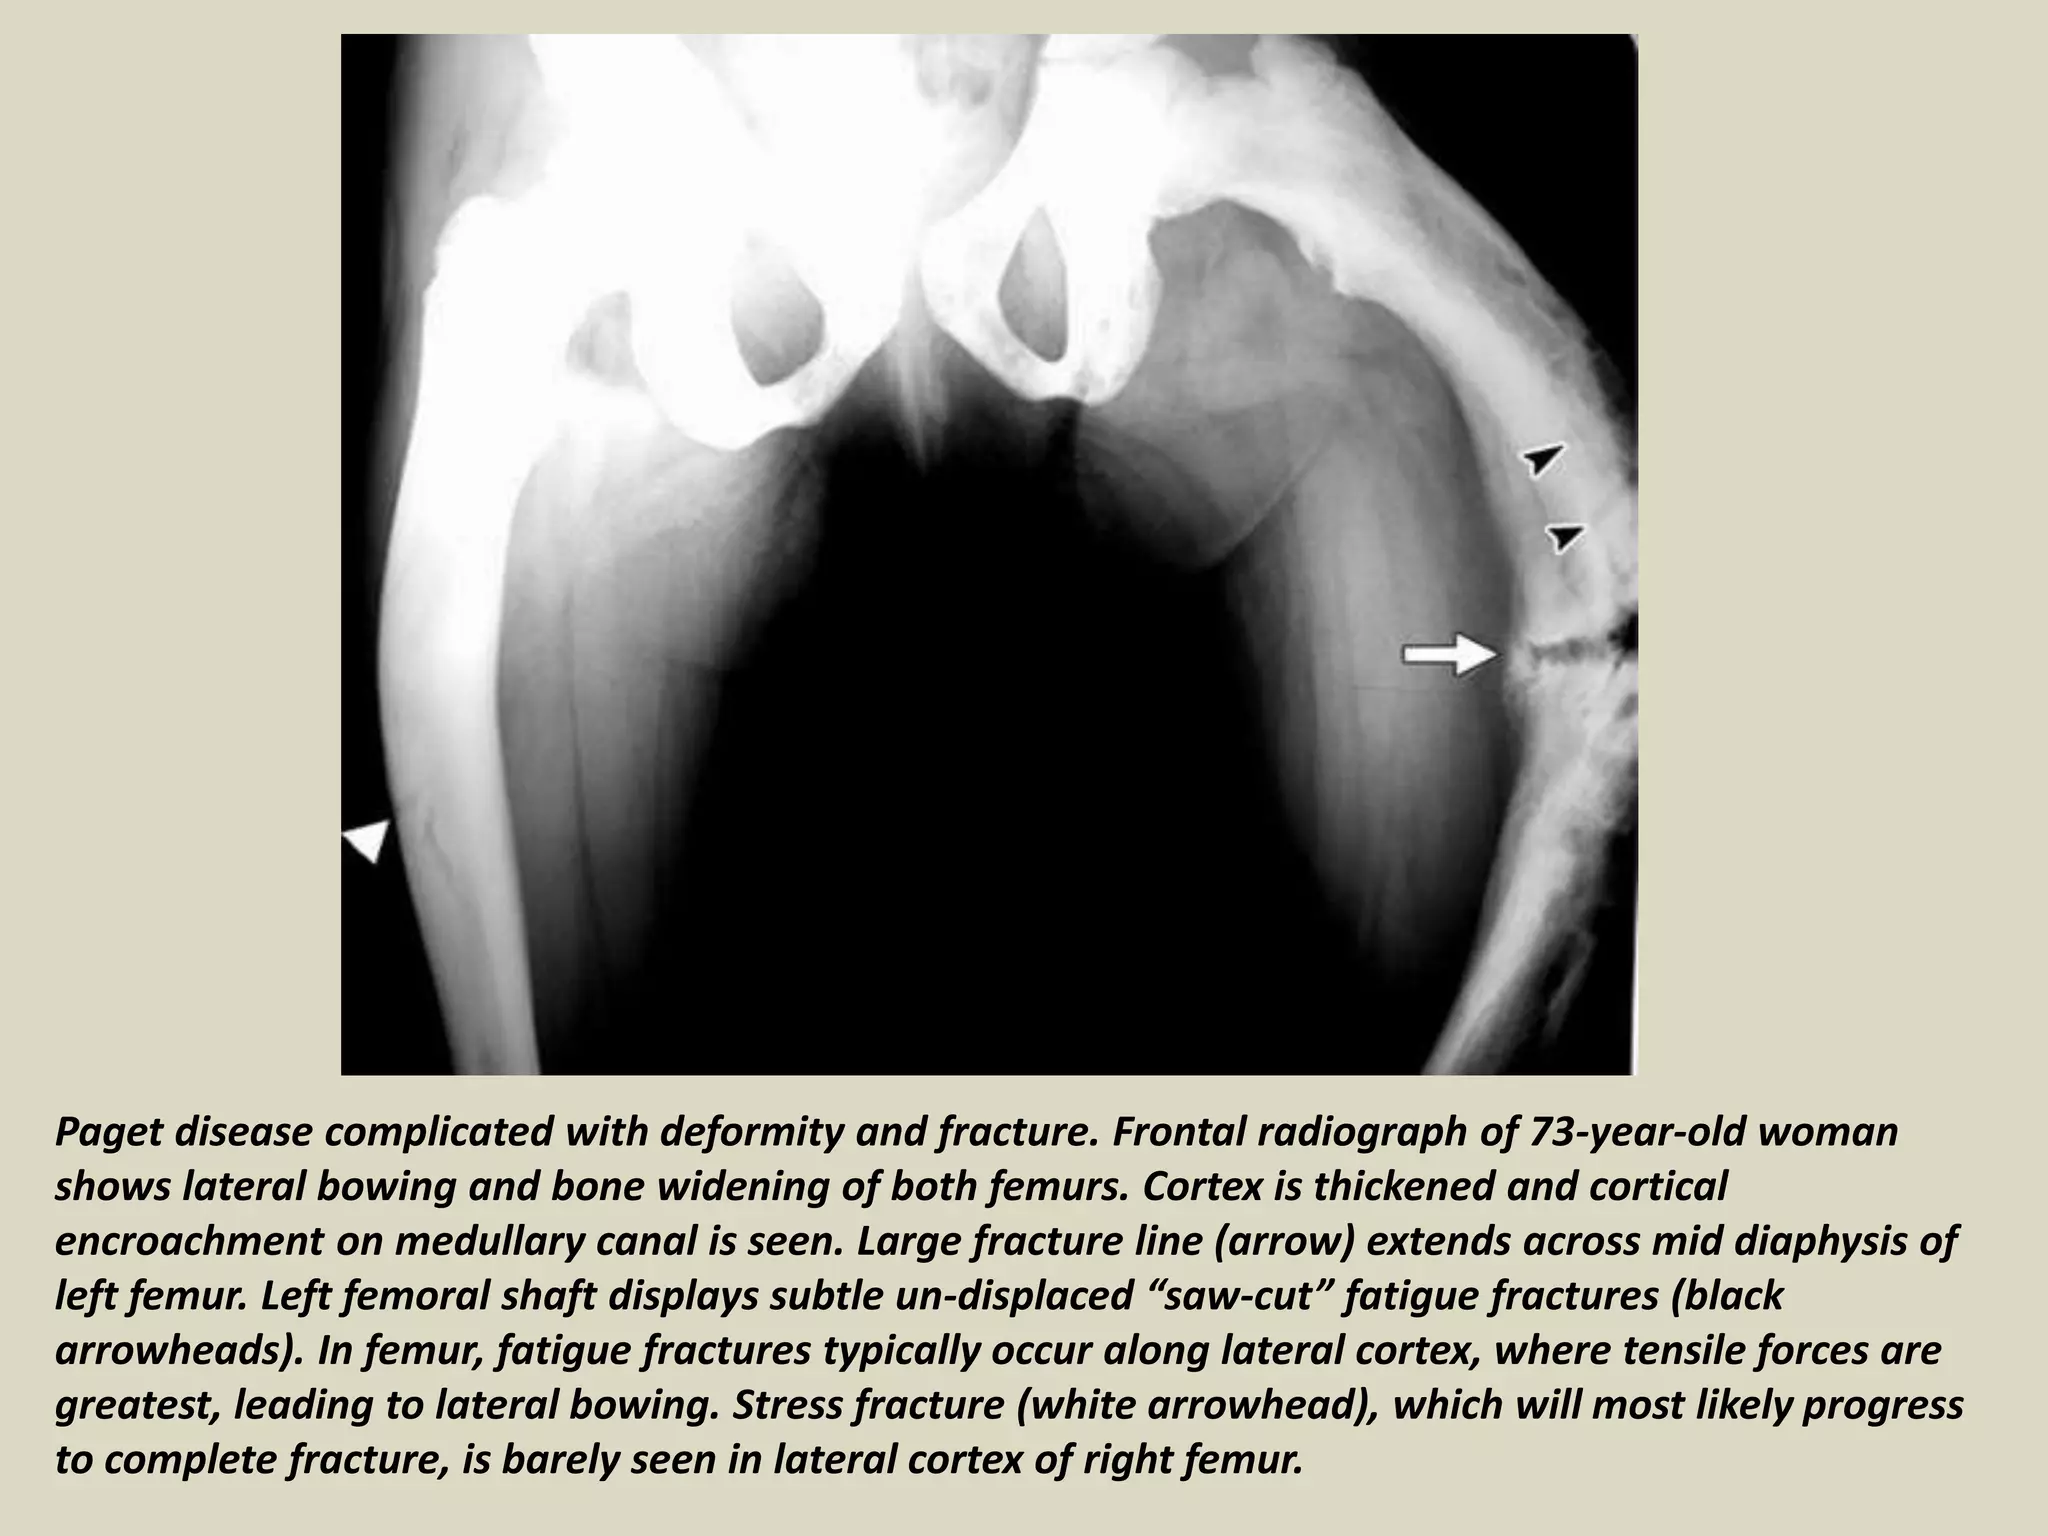

Paget disease complicated with deformity and fracture. Frontal radiograph of 73-year-old woman

shows lateral bowing and bone widening of both femurs. Cortex is thickened and cortical

encroachment on medullary canal is seen. Large fracture line (arrow) extends across mid diaphysis of

left femur. Left femoral shaft displays subtle un-displaced “saw-cut” fatigue fractures (black

arrowheads). In femur, fatigue fractures typically occur along lateral cortex, where tensile forces are

greatest, leading to lateral bowing. Stress fracture (white arrowhead), which will most likely progress

to complete fracture, is barely seen in lateral cortex of right femur.